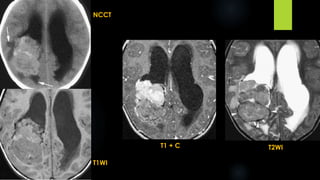

NCCT

T1WI

T1 + C T2WI